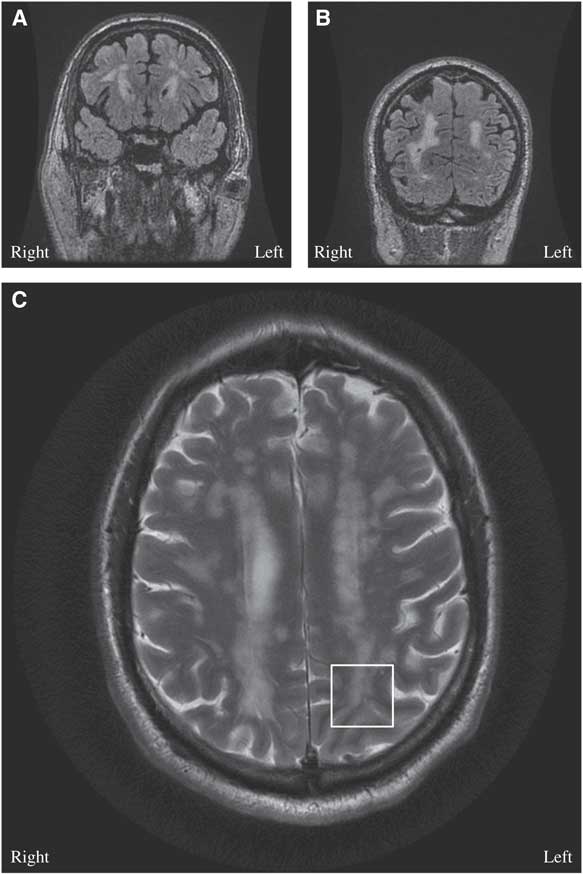

Figure 1 (A, B) Brain MRI coronal T2 Fluid Attenuation Inversion Recovery (FLAIR)-multifocal confluent and discrete subcortical, deep and periventricular lesions are seen involving both cerebral hemispheres, including temporal and occipital lobes. (C) Brain MRI axial T2: few lesions are seen extending through the U fibers and abutting the cortex, notable in the left occipital cortex (white box).

A 68-year-old man presented with a bilateral tonic-clonic seizure. His medical history included migraine with aura, hypertension and dyslipidemia. His father and mother had ischemic strokes in their fifth decade of life. On initial examination, his vitals were stable, but he had post-ictal confusion, transient right homonymous hemianopsia and mild right-sided Todd’s paresis. General systems examinations were unremarkable. MRI of the head showed multifocal confluent white matter lesions (Figures 1A-1B) with a few short association (U) fibers abutting the cortex, notable in the left occipital lobe (Figure 1C). An electroencephalography (EEG) captured a focal seizure originating from the left occipital lobe. Lumbar puncture revealed elevated protein (864 mg/L) without pleocytosis. Serum metabolic, infective and inflammatory workups were unremarkable. Levetiracetam 20 mg/kg was loaded intravenously to control his seizures. Subsequent neurological examination demonstrated resolution of his deficits. On further history taking, it was found that the patient had been diagnosed with migraine with aura since the age of 9 years. He described his headache to be bi-frontal, of moderate to severe intensity, throbbing in nature with associated photophobia, phonophobia and nausea. He was experiencing ~4 attacks/year with good relief from taking sumatriptan 100 mg. In some occasions, his headache would be preceded by a visual aura: he would experience either a gradual- or acute-onset right visual field cut followed by a headache. His aura could last between 1 and 4 hours. Six months before presentation, he started to experience frequent isolated visual auras without headaches.

The diagnosis of cerebral autosomal dominant arteriopathy with subacute infarcts and leukoencephalopathy (CADASIL) was entertained on the basis of the history of migraine with aura, family history of early-onset ischemic strokes and diffuse white matter disease on MRI. On genetic analysis, he was found to be heterozygous for a NOTCH3 mutation, C619C>T, and it is pathogenic for CADASIL.Reference Oberstein, Ferrari and Bakker 1 His atypical visual auras were consistent with focal epilepsy originating from the juxtacortical lesions in the left occipital lobe (Figure 1C).

Epilepsy is rare in CADASIL, and it has only been reported in 10% of patients.Reference Dichgans, Mayer and Uttner 3 , Reference Haan, Oberstein and Ferrari 4 The postulated pathophysiology is cortical or juxtacortical involvement—that is, subcortical lacunar infarcts secondary to angiopathy at the gray-white matter junction (Figure 1C).Reference Dichgans, Mayer and Uttner 3 - Reference Bentes, Pimentel and Ferro 5 In a case series with 102 patients with CADASIL, 10 patients had epileptic seizures and nine of them had a history of strokes.Reference Dichgans, Mayer and Uttner 3